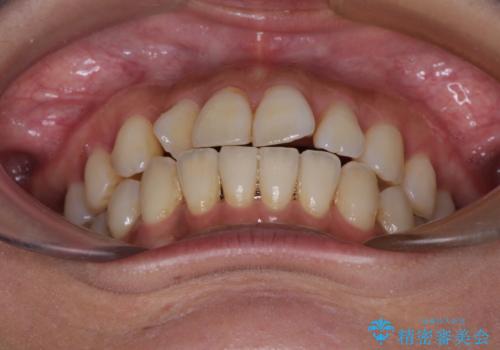

【モニター】上顎前突と奥歯の鋏状咬合 補助装置を用いたインビザライン矯正治療

- 前歯の歯列不正と奥歯の咬みにくさを気にして来院された患者様です。

インビザラインでの矯正治療を希望されていましたが、奥歯の咬み合わせがインビザライン単独では改善困難と判断されたので、補助装置を併用することとしました。

上顎最後臼歯は極端に外側を向いており、下顎骨に対して上顎骨が前方に位置していたため、補助装置により最後臼歯を一気に内側に引き込むとともに、上顎臼歯を後方移動させ、奥歯の咬み合わせが改善した後に、上下インビザラインにより歯列全体を整えていくこととしました。